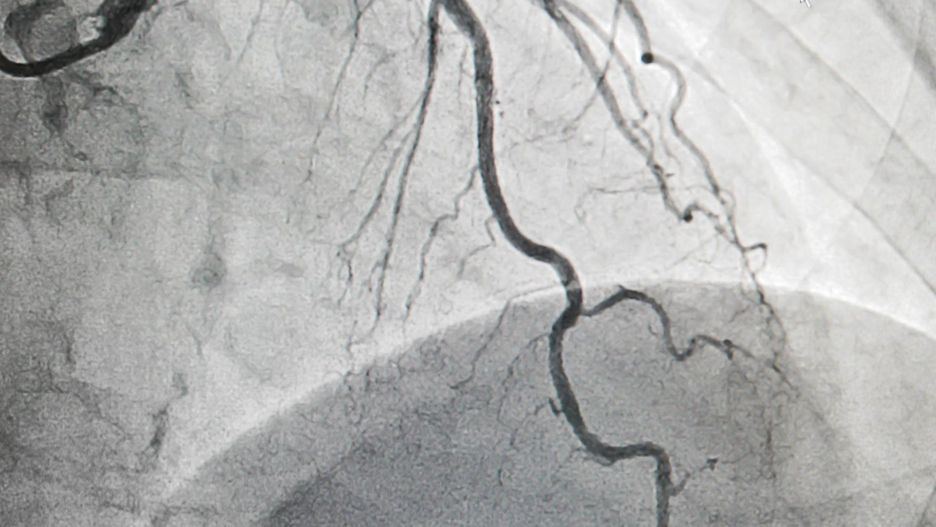

/ 5Jak uniknąć choroby wieńcowej?

Choroby wieńcowej można uniknąć, jeśli zmienisz swój dotychczasowy styl życia i sposób żywienia

Choroby wieńcowej można uniknąć, jeśli zmienisz swój dotychczasowy styl życia i sposób żywienia © (123rf.com) Choroby wieńcowej można uniknąć, jeśli zmienisz swój dotychczasowy styl życia i sposób żywienia

Choroby wieńcowej można uniknąć, jeśli zmienisz swój dotychczasowy styl życia i sposób żywienia. Przede wszystkim zrezygnuj z papierosów i alkoholu na rzecz częstszego ruchu. Unikaj słodkich gazowanych napojów, wysoko przetworzonych produktów, tłustych mięs i fast foodów.

Zamiast nich przygotowuj posiłki z dużą ilością warzyw, chudego mięsa i ryb. Pij zioła, wodę i herbatę. Kawę z umiarem. I co najważniejsze, jeśli poczujesz, że twój organizm nie pracuje prawidłowo, nie zwlekaj – od razu umów się do lekarza.